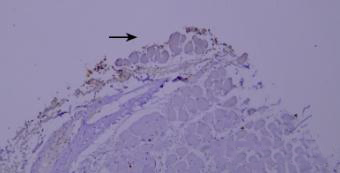

7.干片

干片导致的假阴性(黑色箭头区域)。

优化建议:

加入Tween-20的缓冲液能够更好地防止切片干燥。

8.边缘效应

边缘效应造成的非特异性染色(黑色箭头区域)。

组织切片与玻片黏贴牢固,试剂完全覆盖组织防止干片,加入Tween-20的缓冲液能够更好地防止边缘效应。